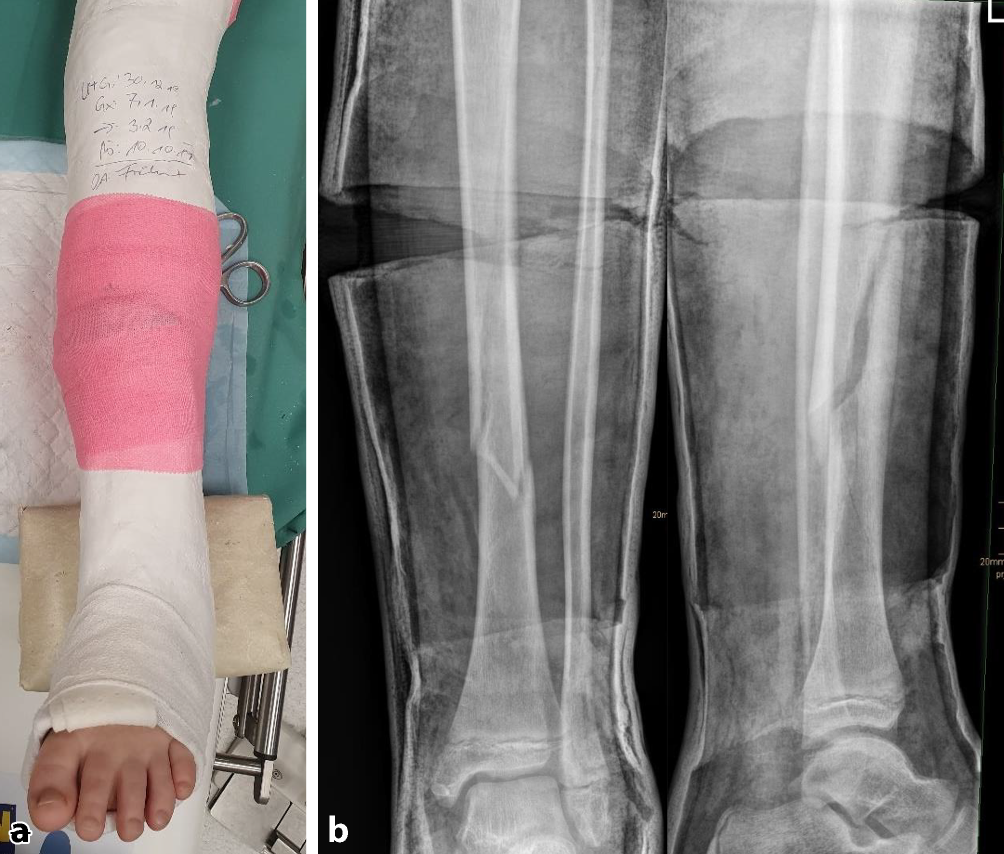

Abb. 2

Gipsanlage am Unterschenkel. Um eine ausreichende Hebelwirkung zu erzielen, ist für die Gipskeilung am Unterschenkel ein Oberschenkelgips mit Streckstellung im Kniegelenk erforderlich. Ventralseitiges Einlegen eines dehnbaren Filzstreifens, faltenfreies Anlegen des Strumpfes. Anbringen des Klebefilzes an prädisponierten druckgefährdeten Stellen, standardmäßig Innen- und Außenknöchelregion und ggf. Tuberositas tibiae. Zum Schutz vor Druckstellen bei Korrektur einer Retrokurvationsfehlstellung zusätzlich Polsterung auch am Fußrücken und im Bereich der Ferse. Zirkuläres Positionieren eines rund 12 cm breiten Filzstreifens an der voraussichtlichen Keilungsstelle (a). Applikation von Watte am proximalen und distalen Gipsende. Als nächster Schritt wird eine zirkuläre Gipsbinde dünnschichtig aufgetragen. Dann Anlegen der bis zum proximalen Gipsende reichenden dorsalen Longuette, zusätzliche Verstärkung durch steigbügelartig aufgelegte zweite Gipslonguette, die bis zum Kniegelenk reicht. Vervollständigung durch zirkuläre Gipsrollen, wobei der Strumpf an den beiden Gipsenden vor der letzten Gipsbinde umgeschlagen und durch diese mitgefasst wird. Wichtig ist ein gefühlvolles Anmodellieren des Gipsverbandes entgegen der bestehenden oder zu erwartenden Fehlstellung, meist Varus bei primär unverschobenen isolierten Tibiaschaftfrakturen (b). Zur Vermeidung von unnötigen, die Keilung erschwerenden Zwischenräumen sollte der Gips bündig angelegt und bis zur Aushärtung permanent in Position gehalten werden. Zuletzt erfolgt zur Eingrenzung des möglichen Keilungsareals die Einzeichnung der Höhe des eingelegten zirkulären Filzstreifens. Idealerweise sind für Gipsanlage an der unteren Extremität ein Arzt, ein Gipsassistent und eine zusätzliche Hilfsperson zur Stabilisierung des Kniegelenks vonnöten